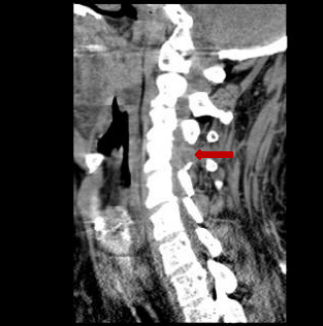

术前脊髓造影后颈椎CT。

颈椎间盘突出明显。